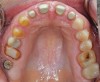

Fig 7. Occlusal view on immediate insertion.

Figure 7

After milling in the Amann Girrbach Ceramill Motion 2 is completed, the restorations were seated on the master cast to verify contacts and occlusion.

All restoration margins were thinned down and anterior shapes were finalized and texturized.

Polishing of all restorations was carried out utilizing Komet composite polishing wheels (kometusa.com) and a final luster was applied via a Robinson wheel and Cosmedent Enamelize composite polishing paste (cosmedent.com).